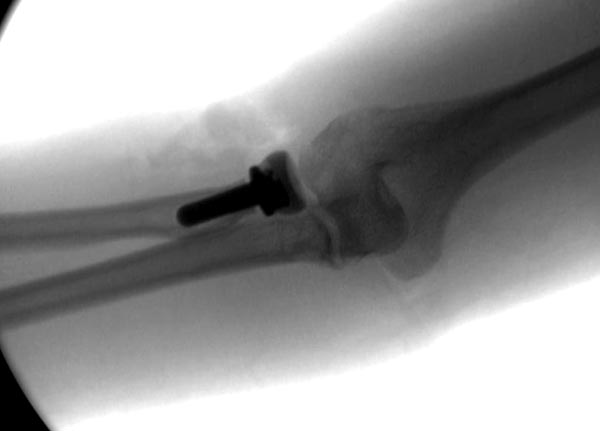

В первом случае перелом Монтеджи, где доперационно сделано оценка положения головки к остальным элементам под рентгеном. Учитывая правильность взаимотношении произведена фиксация только локтевого отростка, Второй случай, заменена на протез, и третий, кроме фиксации головки - реконструкция capitellum латерального мыщелка.

Популярная в странах СНГ резекция головки луча в наших условиях делается очень редко, потому что без упора луча могут проявиться симптомы нестабильности в дистальном радио-ульнарном сочленении. Реконструкция с сохранением головки дает лучший результат, но не всегда возможна.

Видел больных с резицированной головкой, который подтягивался на руке без проблем, а также проблемных после фиксации. Поэтому трудно судить, хотя при подозрении на Essex-Lopresti, когда повреждается межкостная мембрана на всем протяжении, надо протезировать - пространство!